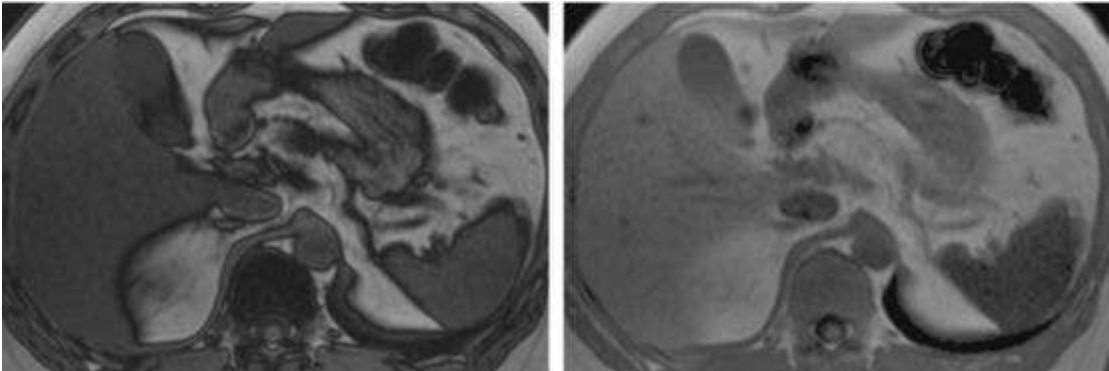

*T1WI同反相位成像:这是MR诊断脂肪肝的“金标准”。在T1WI同相位图像上,脂肪肝的信号强度与正常肝组织相似;而在反相位图像上,脂肪肝的信号强度会明显降低。

(图片说明:左图为T1WI同相位图像,右图为T1WI反相位图像,可见脂肪肝在反相位图像上信号强度明显降低)